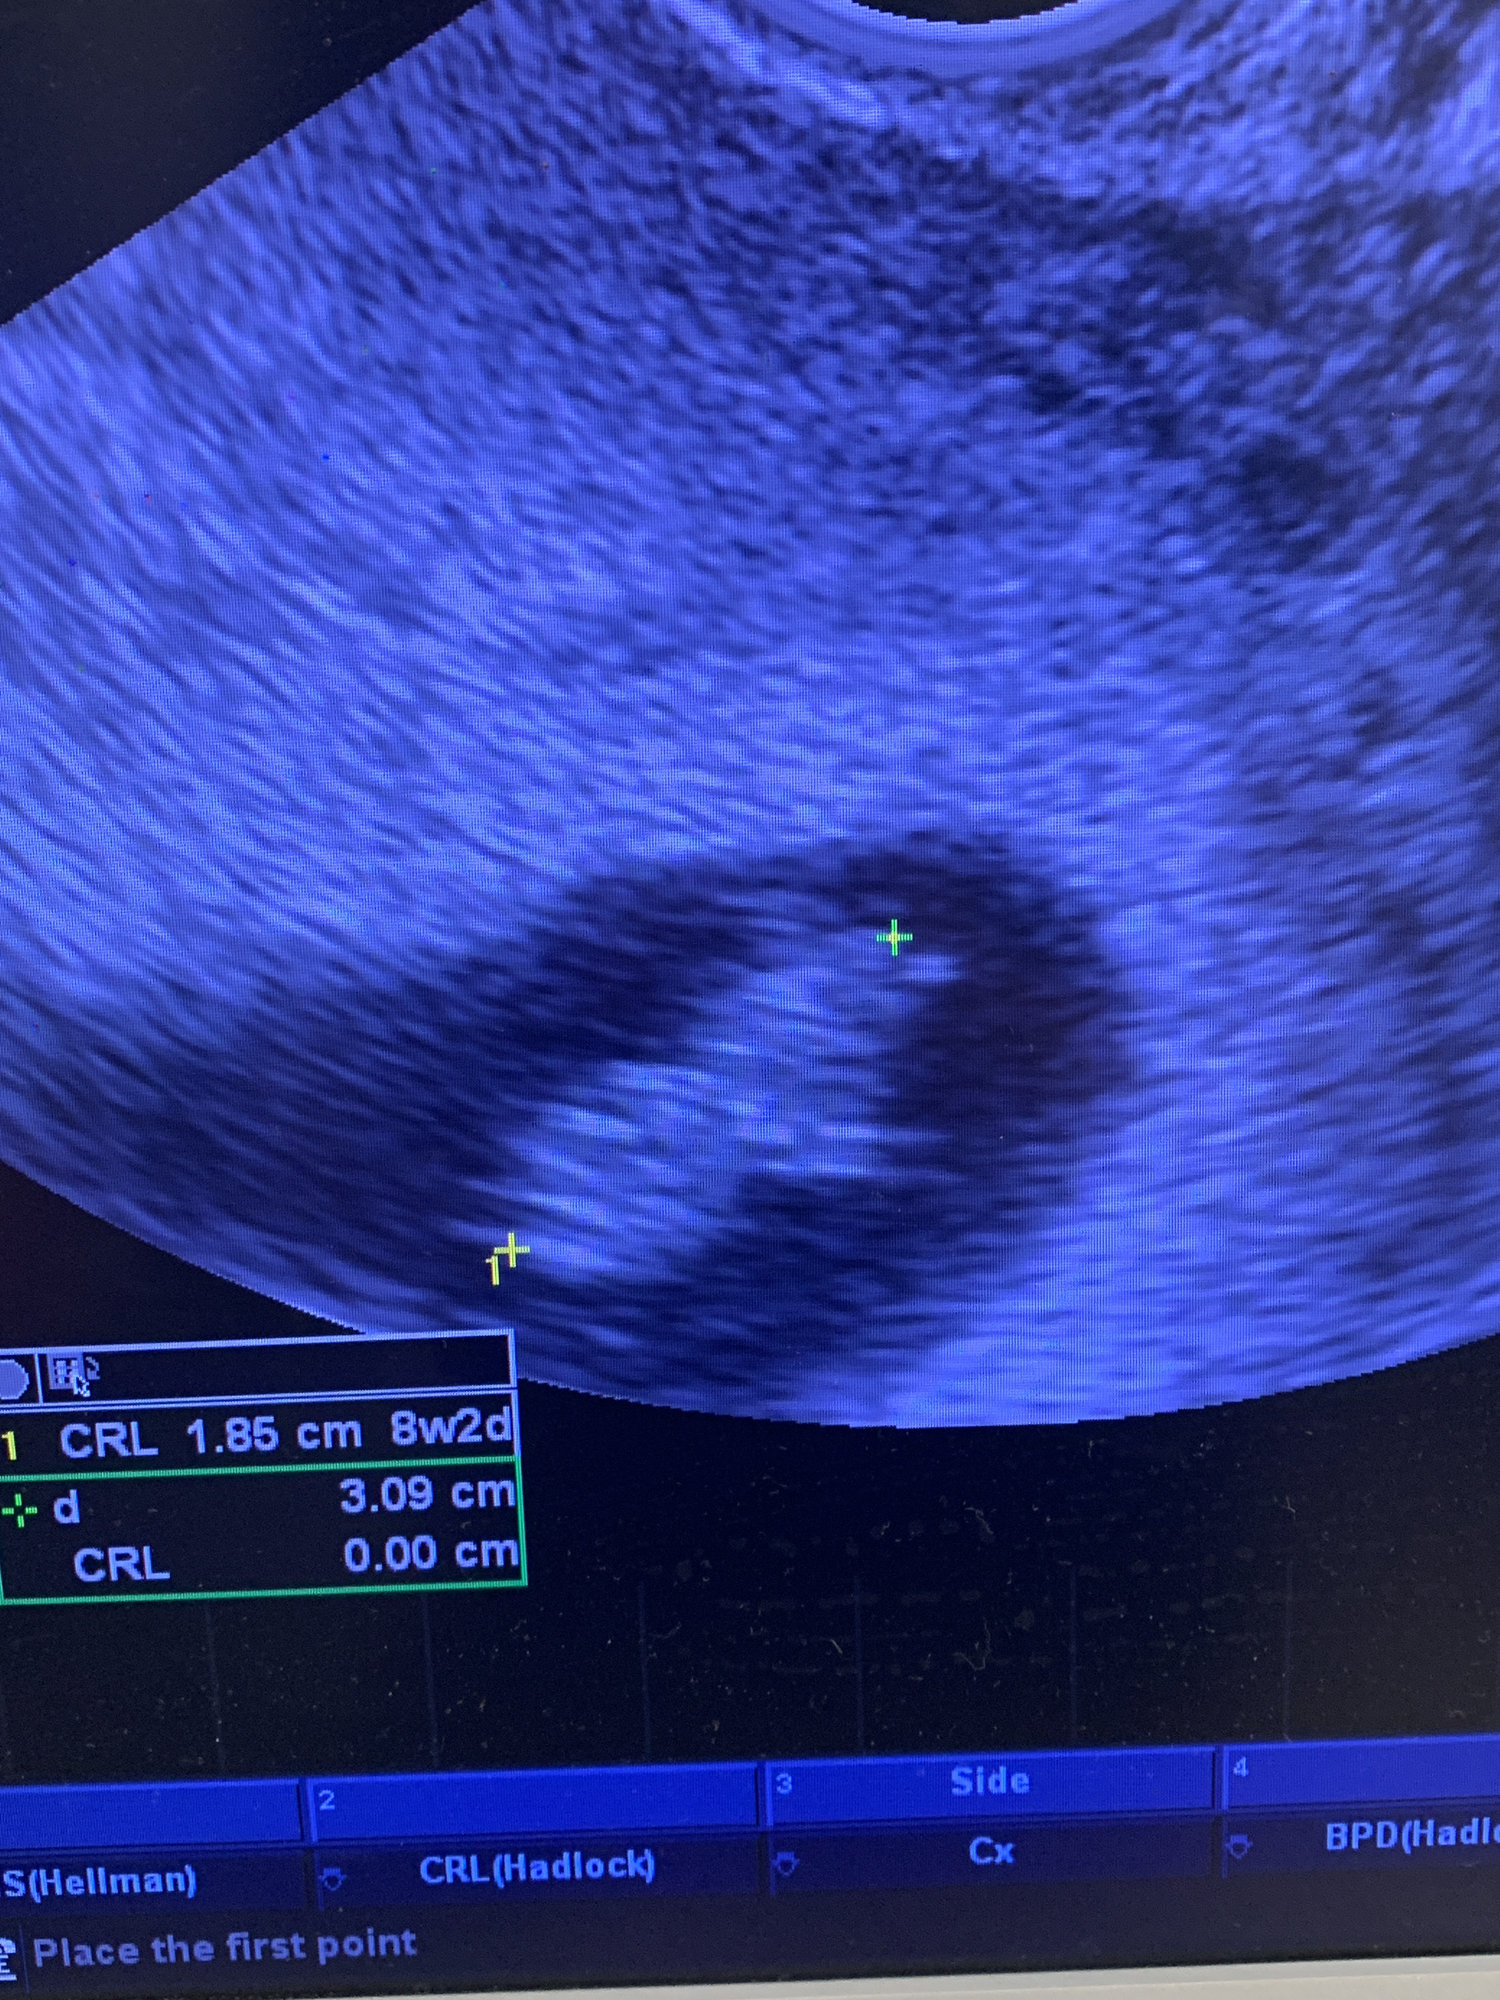

Thank you @therealbitts I know all babies grow at different rates, so rationally it may be too early to worry, but waiting another week to see if the baby is still growing is extremely difficult. Praying we are just off to a slow start and everything is still progressing.